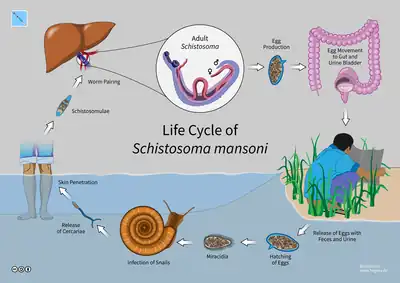

The life cycle of schistosomes includes two hosts: humans as definitive hosts, where the parasite undergoes sexual reproduction, and snails as intermediate hosts, where a series of asexual reproduction takes place. S. mansoni is transmitted through water, where freshwater snails of the genus Biomphalaria act as intermediate hosts. The larvae are able to live in water and infect the hosts by directly penetrating the skin. Prevention of infection is done by improved sanitation and killing the snails. Infection is treated with praziquantel.

Life cycle

Intermediate host

After the eggs of the human-dwelling parasite are emitted in the faeces and into the water, the ripe miracidium hatches out of the egg. The hatching happens in response to temperature, light and dilution of faeces with water. The miracidium searches for a suitable freshwater snail belonging to the genus Biomphalaria. In South America, the principal intermediate host is Biomphalaria glabrata, while B. straminea and B. tenagophila are less common.[34] A land snail Achatina fulica was reported in 2010 to act as a host in Venezuela.[35] In Africa, B. glabratra, B. pfeifferi, B. choanomphala and B. sudanica act as the hosts;[36] but in Egypt, the main snail host is B. alexandrina.[37]

Miracidia directly penetrate the soft tissue of snail. Inside the snail, they lose their cilia and develop into mother sporocysts. The sporocysts rapidly multiply by asexual reproduction, each forming numerous daughter sporocysts. The daughter sporocysts move to the liver and gonads of the snail, where they undergo further growth.[38] Within 2–4 weeks, they undergo metamorphosis and give rise to fork-tailed cercariae. Stimulated by light, hundreds of cercariae penetrate out of the snail into water.[39]

Definitive host

The cercaria emerge from the snail during daylight and they propel themselves in water with the aid of their bifurcated tail, actively seeking out their final host. In water, they can live for up to 12 hours, and their maximum infectivity is between 1 and 9 hours after emergence.[40] When they recognise human skin, they penetrate it within a very short time. This occurs in three stages, an initial attachment to the skin, followed by the creeping over the skin searching for a suitable penetration site, often a hair follicle, and finally penetration of the skin into the epidermis using cytolytic secretions from the cercarial post-acetabular, then pre-acetabular glands. On penetration, the head of the cercaria transforms into an endoparasitic larva, the schistosomule. Each schistosomule spends a few days in the skin and then enters the circulation starting at the dermal lymphatics and venules. Here, they feed on blood, regurgitating the haem as hemozoin.[41] The schistosomule migrates to the lungs (5–7 days post-penetration) and then moves via circulation through the left side of the heart to the hepatoportal circulation (>15 days) where, if it meets a partner of the opposite sex, it develops into a sexually mature adult and the pair migrate to the mesenteric veins.[42] Such pairings are monogamous.[43]

Male schistosomes undergo normal maturation and morphological development in the presence or absence of a female, although behavioural, physiological and antigenic differences between males from single-sex, as opposed to bisex, infections have been reported. On the other hand, female schistosomes do not mature without a male. Female schistosomes from single-sex infections are underdeveloped and exhibit an immature reproductive system. Although the maturation of the female worm seems to be dependent on the presence of the mature male, the stimuli for female growth and for reproductive development seem to be independent from each other.

The adult female worm resides within the adult male worm's gynaecophoric canal, which is a modification of the ventral surface of the male, forming a groove. The paired worms move against the flow of blood to their final niche in the mesenteric circulation, where they begin egg production (>32 days). The S. mansoni parasites are found predominantly in the small inferior mesenteric blood vessels surrounding the large intestine and caecal region of the host. Each female lays approximately 300 eggs a day (one egg every 4.8 minutes), which are deposited on the endothelial lining of the venous capillary walls.[44] Most of the body mass of female schistosomes is devoted to the reproductive system. The female converts the equivalent of almost her own body dry weight into eggs each day. The eggs move into the lumen of the host's intestines and are released into the environment with the faeces.